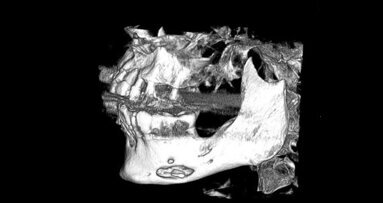

W przeszłości planowanie umieszczenia implantu dokonywało się na podstawie zdjęcia pojedynczego zęba lub zdjęcia panoramicznego, co obarczone było niską precyzją.5 Obecnie z pomocą przychodzą systemy, które pozwalają na wirtualne planowanie leczenia implantoprotetycznego z wykorzystaniem tomografii komputerowej wiązki stożkowej. CBCT jest techniką obrazowania medycznego, gdzie podstawą każdego badania są przekroje cyfrowe. Na podstawie tych przekrojów uzyskiwany jest obraz dwu- lub trójwymiarowy badanego obszaru.6 Zdolność oprogramowania komputerowego do przeformatowania cyfrowych tomogramów na obraz 2D i 3D z dokładnością wymiarów w stosunku 1:1 pozwala na dokładne zaplanowanie umiejscowienia implantu.7

Obecność odpowiedniej jakości i ilości kości jest niezbędna dla powodzenia zabiegu wszczepienia implantu. Do oceny czy istnieją odpowiednie warunki kostne oraz zaplanowania całego leczenia implantoprotetycznego wykorzystano systemy oparte na tomografii komputerowej wiązki stożkowej (CBCT). Oprogramowanie CS 3D Imaging Software pozwoliło wykonać trójwymiarową diagnostykę obszaru dla wszczepu implantologicznego. Dzięki pomiarom wyrostka zębodołowego możliwy był wybór odpowiedniego systemu i rozmiaru implantu.